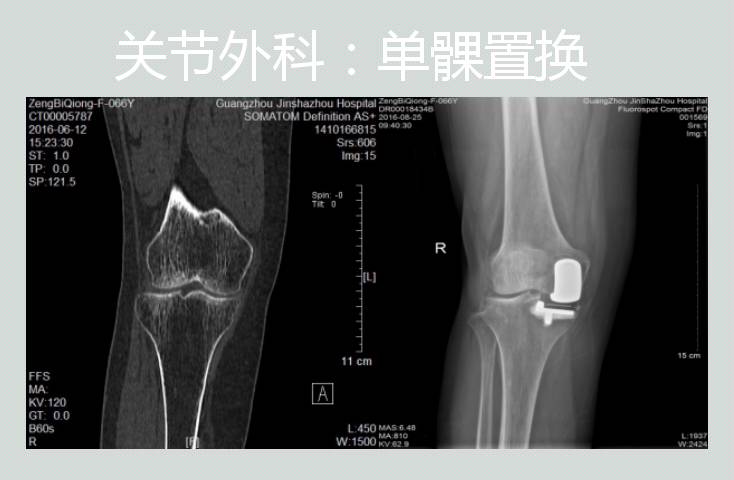

各种关节疾病的诊断与外科治疗:髋、膝关节的人工关节置换及翻修手术、骨关节炎、类风湿性关节炎、强直性脊柱炎的髋膝关节病变的外科治疗、股骨头缺血性坏死的外科治疗、股骨颈骨折和股骨粗隆间骨折的外科治疗、先天性髋关节脱位的诊断与治疗,各种小儿四肢骨关节病变的治疗、关节镜的检查与微创治疗等。